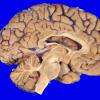

1A2 NCL (Case 1) gross 3

1A3 NCL (Case 1) gross 1